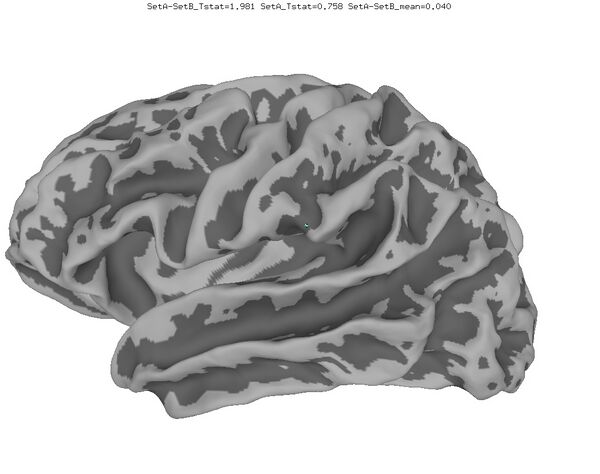

Anatomical Data

New

Old

Functional data of the Mouth vs. Eye contrast mapped to the average surface. It is hard to quantify the difference, but one way is to compare the maximum statistical values; with better intersubject alignment, these would presumably increase.

1. NEW: Max t-value for Mouth: 9.3 Eye:10.1 Eye vs Mouth: 5.6

2. OLD: Max t-value for Mouth: 7.9 Eye:8.8 Eye vs Mouth: 5.8

data from Zhu LL, Beauchamp MS. Mouth and Voice: A Relationship between Visual and Auditory Preference in the Human Superior Temporal Sulcus. Journal of Neuroscience 8 March 2017, 37 (10) 2697-2708; DOI: https://doi.org/10.1523/JNEUROSCI.2914-16.2017. Click here to download the PDF. Surface averages were not used in this paper so the bug did not affect the published results.